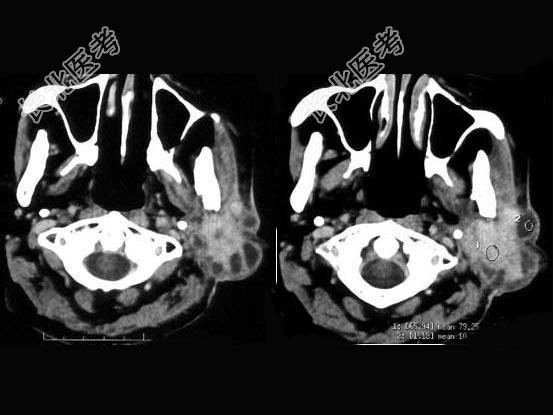

- 单项选择题女,55岁, 鼻咽癌放疗15年,近1周左耳根部肿胀, 无发热,PE: 左耳根部皮下扪及三个结节,有波动感和轻压痛, CT如图所示,最可能的诊断是 ( )

A、左腮腺腺瘤

B、左腮腺混合瘤

C、左腮腺腺淋巴瘤

D、左腮腺恶性混合瘤

E、左腮腺蜂窝织炎